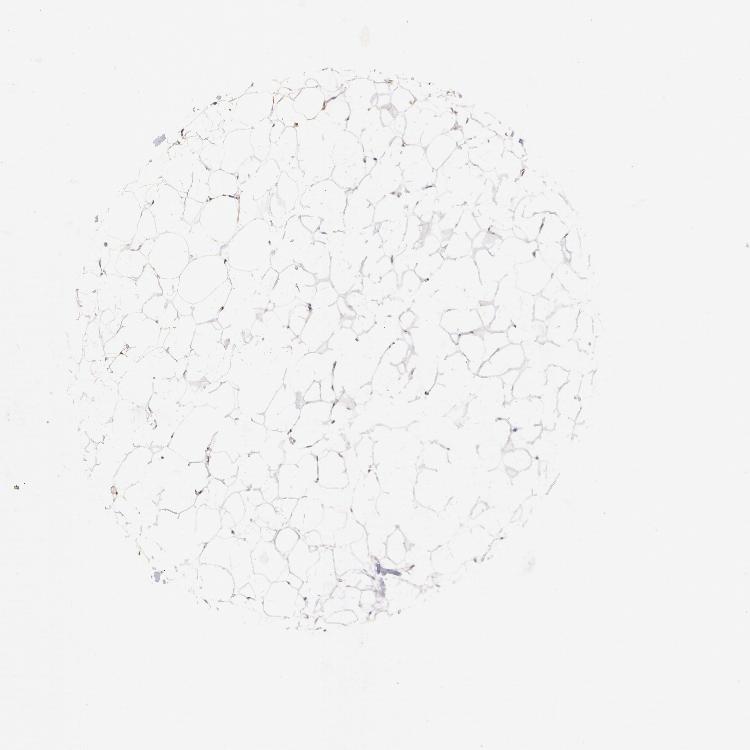

ADIPOSE TISSUE - Antibody stainingi

Antibody staining in the annotated cell types in the current human tissue is reported as not detected, low, medium, or high, based on conventional immunohistochemistry profiling in selected tissues. This score is based on the combination of the staining intensity and fraction of stained cells.

Each image is clickable and will lead to virtual microscopy that enables deeper exploration of all samples and also displays staining intensity scores, fraction scores and subcellular localization as well as patient and tissue information for each sample.

Antibody HPA000903Antibody CAB006244

Adipocytes MediumMedium